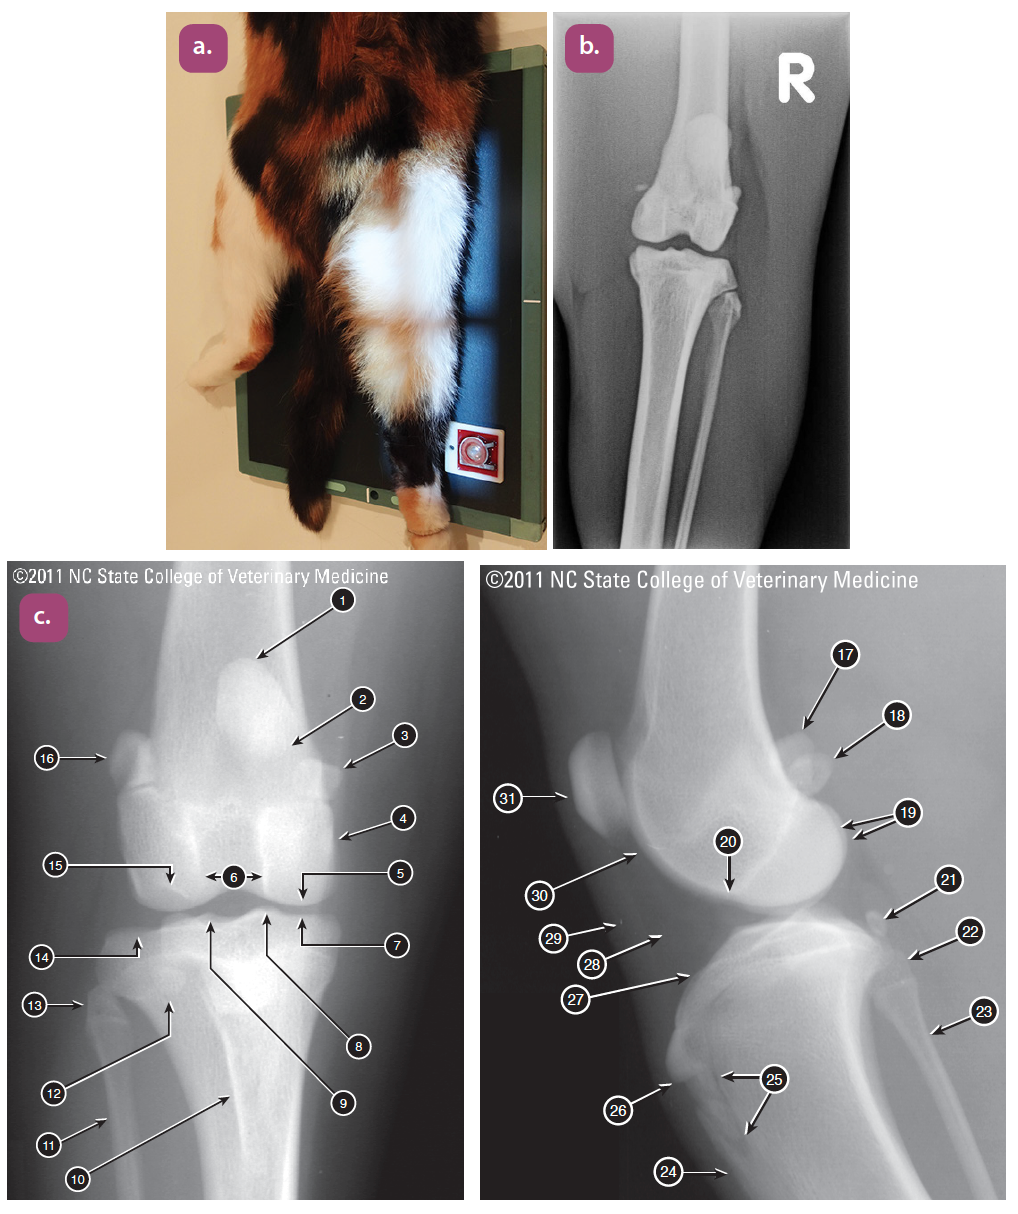

mediolateral projection of the tibia

caudocranial projection of the tibia and fibula